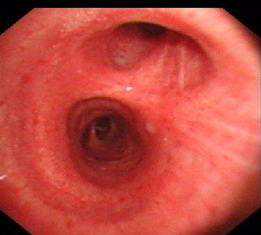

纤支镜检查镜下均以非特异性炎症改变为主(如图9-10),病理示淋巴细胞、中性粒细胞等炎性细胞侵润(图11)。对于肺隔离症的诊断或鉴别诊断所起作用较小。

图9右主支气管管腔黄白色分泌物,粘膜表面稍充血肿胀

图10左下叶支气管内前基底段纤支镜下表现